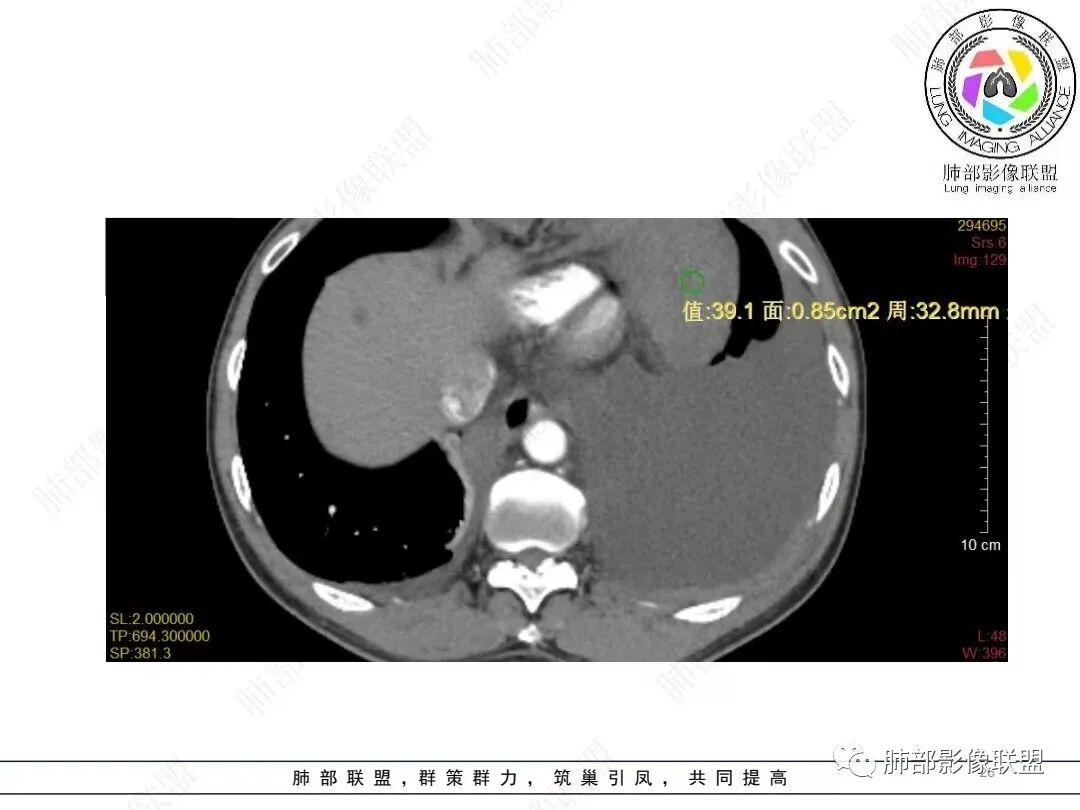

目前的图:主要是胸部的病灶。胸膜弥漫斑块状增厚。强化明显,内部血管漂浮。前纵隔部分病灶强化偏低。

就胸部病灶的特性,好像与甲状腺的不一致。强化、内部的坏死囊变不相符。我认为甲状腺来源的几率不高。

2.影像学特点:病变范围相当广泛,多发块状影累及纵隔、胸膜、前胸壁(胸大肌下)、前上腹壁等。胸膜弥漫性斑状增厚为主,明显强化,纵隔旁椭圆形块影较密实,沿胸膜分布趋势,未见支气管等结构进入。后纵隔块影较大,占位效应明显,肺静脉受累狭窄。双侧胸腔积液。

甲状腺右叶相对低密度结节影,边界清楚,不均匀分隔样强化,经验上分析与胸部病灶缺乏关联性。